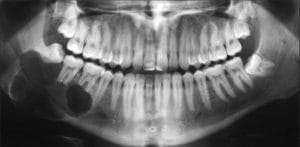

Nhiều người bị u men răng mà không biết

Thấy mặt tự dưng lệch hẳn sang một bên, anh Văn (37 tuổi, Nam Định)...